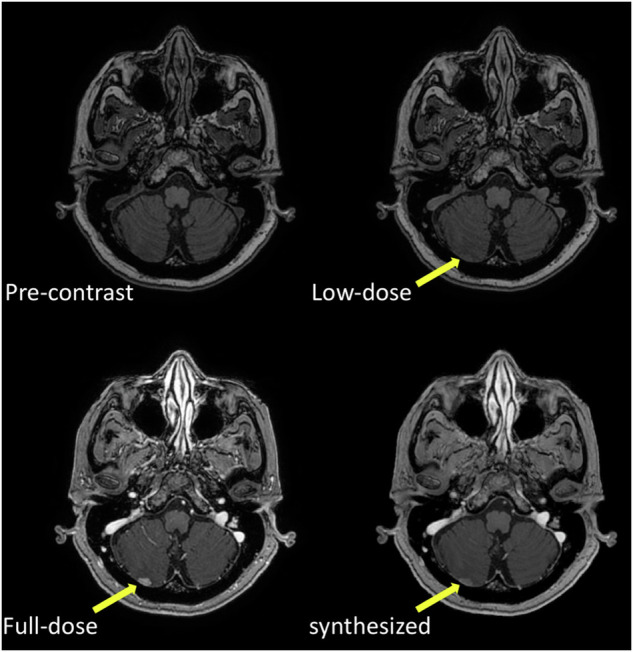

Substantial endeavors have been recently dedicated to developing artificial intelligence (AI) solutions, especially deep learning-based, tailored to enhance radiological procedures, in particular algorithms designed to minimize radiation exposure and enhance image clarity. Thus, not only better diagnostic accuracy but also reduced potential harm to patients was pursued, thereby exemplifying the intersection of technological innovation and the highest standards of patient care. We provide herein an overview of recent AI developments in computed tomography and magnetic resonance imaging. Major AI results in CT regard: optimization of patient positioning, scan range selection (avoiding "overscanning"), and choice of technical parameters; reduction of the amount of injected contrast agent and injection flow rate (also avoiding extravasation); faster and better image reconstruction reducing noise level and artifacts. Major AI results in MRI regard: reconstruction of undersampled images; artifact removal, including those derived from unintentional patient's (or fetal) movement or from heart motion; up to 80-90% reduction of GBCA dose. Challenges include limited generalizability, lack of external validation, insufficient explainability of models, and opacity of decision-making. Developing explainable AI algorithms that provide transparent and interpretable outputs is essential to enable seamless AI integration into CT and MRI practice. RELEVANCE STATEMENT: This review highlights how AI-driven advancements in CT and MRI improve image quality and enhance patient safety by leveraging AI solutions for dose reduction, contrast optimization, noise reduction, and efficient image reconstruction, paving the way for safer, faster, and more accurate diagnostic imaging practices. KEY POINTS: Advancements in AI are revolutionizing the way radiological images are acquired, reconstructed, and interpreted. AI algorithms can assist in optimizing radiation doses, reducing scan times, and enhancing image quality. AI techniques are paving the way for a future of more efficient, accurate, and safe medical imaging examinations.